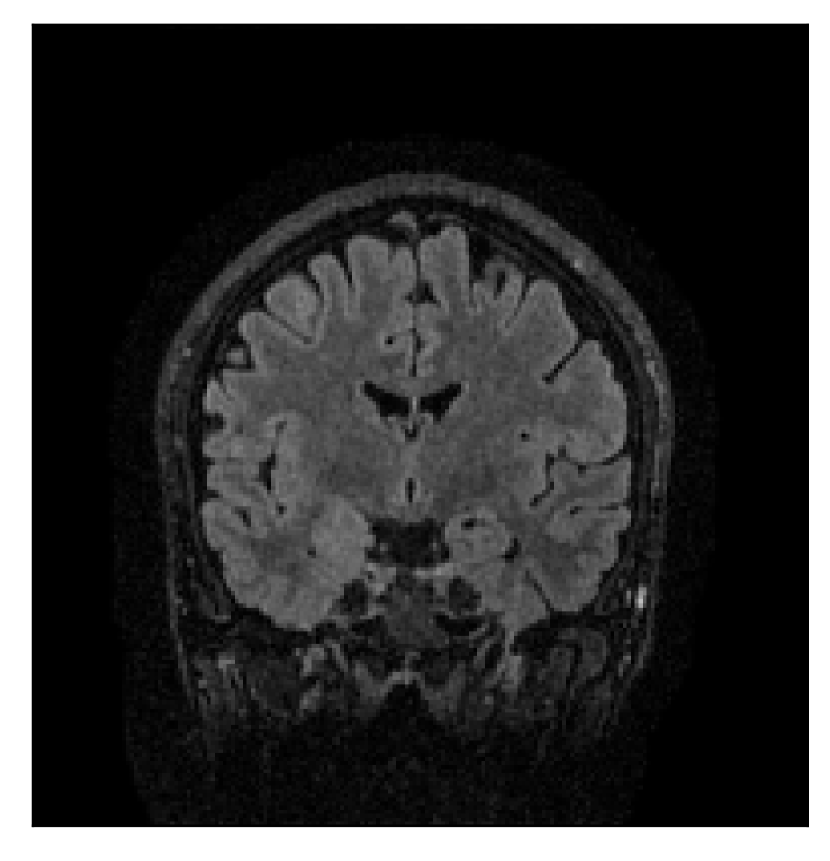

| Section 3.1, Figure 2 | Sagittal | 23.94 | 27.95 | 0.7068 | 0.7936 |

| Coronal | 26.66 | 29.82 | 0.7653 | 0.8332 | |

| Axial | 25.40 | 30.16 | 0.7616 | 0.8490 | |

The motion-corrected full-volume scans were analyzed by a neuroradiologist with 16 years of experience. These were generally deemed of good radiological quality. The motion-related artifacts have been completely removed, and the results are quite close to the ground truth. In Table 3, we organized a more detailed qualitative analysis of the 3D results, geared toward a radiological assessment of the corrected scans.

| Experiment | Contrast | Motion resolution | Blurring | Artifacts | Additional comments |

| Section 3.1, Figure 2 | T2-FLAIR | Completely corrected | Some blurring | No additional artifacts | Good grey white matter differentiation |

4.1 Experiment 1: robustness test

We gather the results for the robustness test described in Section 3.1 (volunteer 1) in Figures 2, 4, and 6 for motion corruption mechanisms associated to one, two, and five changes of position, respectively. Furthermore, we juxtapose the corrected images with varying degrees of corruption in Figure 8. We observe that the proposed method consistently ameliorates the corrupted scan. The quality indexes based on PSNR and SSIM show only a modest decrease in correction quality as a function of motion complexity (Figure 8).

Our experimentation based on volunteer data aimed at assessing the robustness of the correction quality with respect to motion artifacts of increasing complexity. In this study, we equated this complexity to the number of volunteer changes of pose during the acquisition phase. Clearly, this does not fully describe the complexity of motion encountered in practice in the clinic, but it only constitutes a preliminary step in that direction. Nevertheless, the results described in Section 4.1 support the indication that the retrospective motion correction of T2-FLAIR weighted images based on a T1 reference contrast is quite robust in terms of reconstruction quality, with only minor degradations in terms of contrast and resolution.